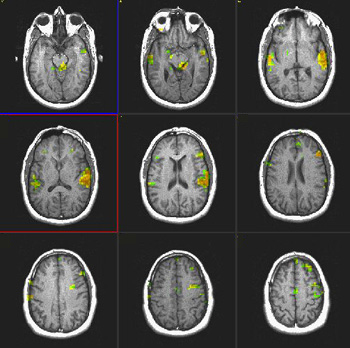

Studies in Late Bilinguals

| Subject |

Right handed 34 year-old-woman. Native language: Spanish

|

| Paradigm |

Type: Verbal fluency task

ON: Retrieve verbs related to presented nouns

OFF Spell given words |

| Statistics |

| Statistical method |

P Value |

Z score |

| T-Test |

0.0001 |

3.8 |

| Images |

Spanish

English

| Activation |

There is activation of Broca's area in both languages. The right thalamic activation is noted only in the second language. There is also greater activation of the right inferior frontal gyrus in the second language than in the mother language. SMA is more pronounced on the right in both languages. |